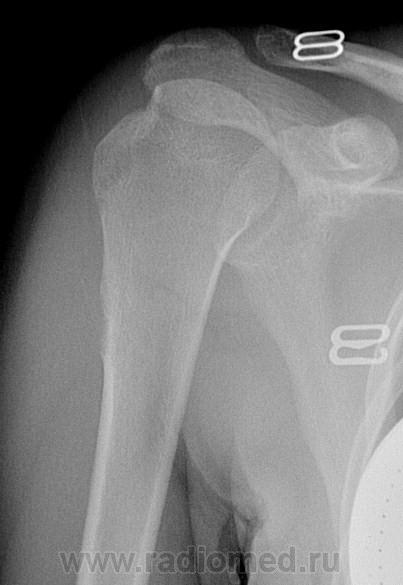

Прошу высказать ваше мнение. Девочка 15 лет поступила в детское травм отделение. Диагноз - привычный вывих правой плечевой кости. 1,5 года назад довольно серьезная трама плеча- со слов - разрыв связки... После чего до сегодняшнего дня 8 раз происходил вывих. Выполнялось вправление. На рентгенограммах - данные изменения в проксимальной трети диафиза по наружной поверхности. В данной области локальных болей при надавливании, ночных болей нет. Кожный покров не изменен. Ничего не пальпируется. Объем руки не увеличен. Как по вашему можно трактовать эти изменения и чем они могут быть.

А снимков с прошлой травмы нет? Похоже, ранее был был перелом большого бугорка, возможно, переломовывих. А теперь - последствия травмы в виде привычного вывиха.

есть краевой дефект головки- признак привычного вывиха.

Ну и прерывистость  наружного контура в/3 плеча.

Коллеги , изменения ИМЕННО В ПРОКСИМАЛЬНОЙ ТРЕТИ ДИАФИЗА ПО НАРУЖНОЙ ПОВЕРХНОСТИ ввиде неровности контура - посттравматические изменения? не может ли это быть например опухолевым образованием? Валентин Львович , укажите ,пожалуйста, что вы имеете ввиду.

Бугристость в месте прикрепления дельтовидной мышцы. На мой взгляд, вряд ли нуждается в биопсии.

Понятно, что это бугристось,но что-то она как-то не внушает доверия.Кортикальный слой -то не совсем четкий-ровный.Поддержу Валентина Львовича.

Коллеги, сегодня был на операции (по поводу привычного вывиха и за одно ревизии данной области). Типичная картина остеохондромы. Взята гистология. Неровность контура - скорее всего основание опухоли из костной ткани, а хрящевая "шапочка" для рентген лучиков была прозрачна. Размеры опухоли как раз соответствовали изменениям в диафизе. Опухоль была маленькая - по этому скорее всего и не пальпировалась ( хотя наверно при старании удалось бы)))

Спасибо за новость.Ждем верификацию. А дельтовидная бугристость намного ниже.